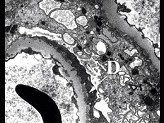

- 单项选择题图-1可见上皮下少量嗜复红蛋白沉积(1)(Masson),图-2可见上皮下少量电子致密物沉积沉积(D), 上皮细胞足突融合,其病理可诊断为 ( )

A、Ⅰ期膜性肾病